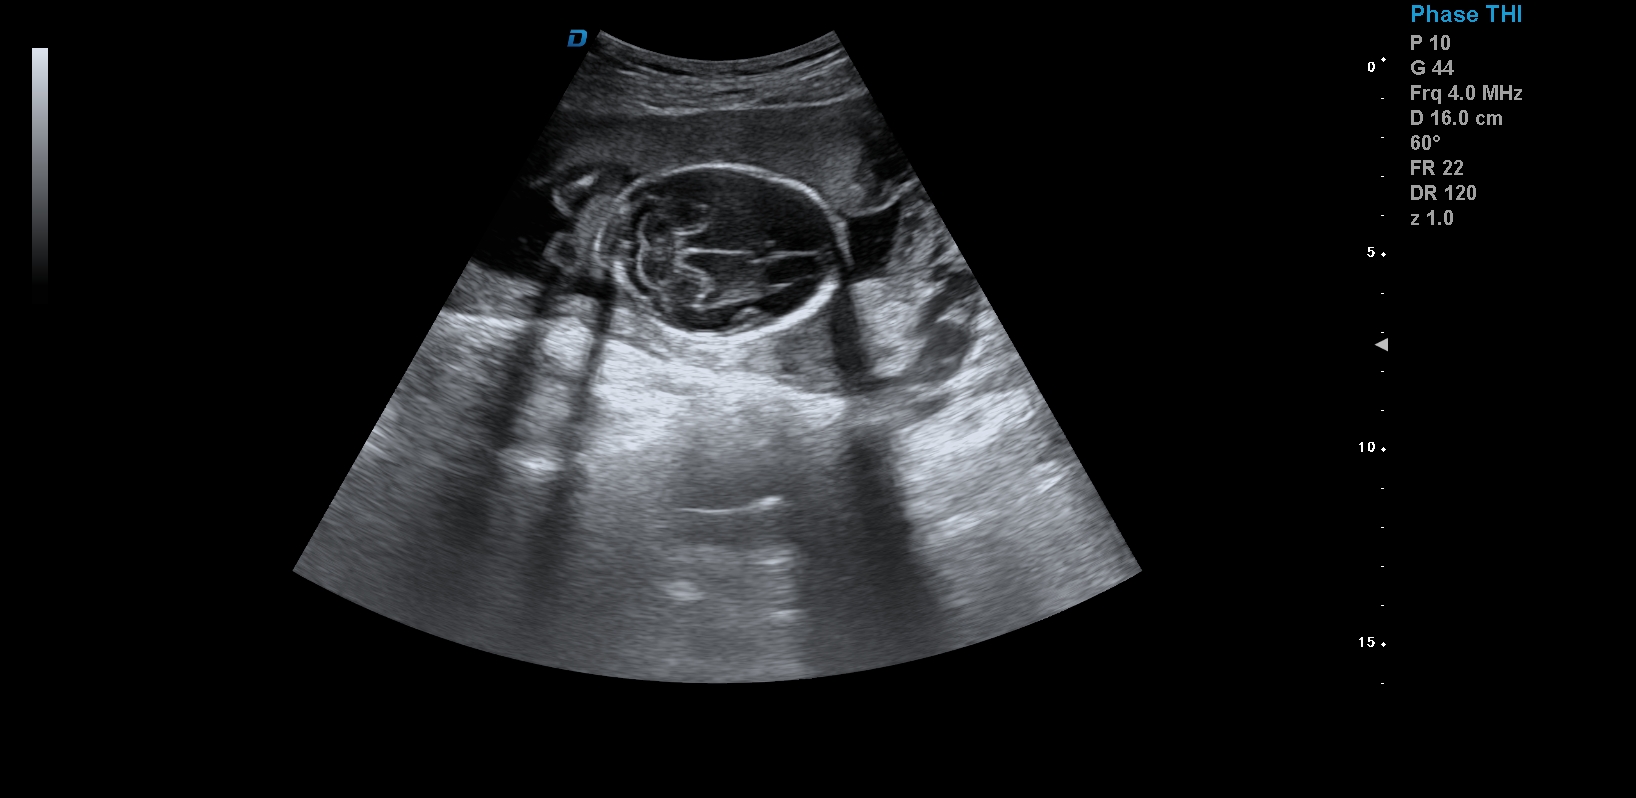

四維彩超,見證生命最初的感動

首先,四維彩超檢查是采用高清晰度的彩超儀對胎兒進行各個心臟器官及組織的一次全面檢查,可以立體顯示胎兒的發育情況,胎兒在子宮內的任何狀態都可以觀察到。對胎兒畸形能夠早診斷,及時地做出相應的措施,以達到優生優育的標準。

四維彩超不但成像清晰,更是在三維的基礎之上附加時間這個矢量。這就在排畸的同時能時刻觀察寶寶在宮內的一舉一動,吃手指、打哈欠、吮吸……寶寶在宮內憨態可掬,讓孕媽媽母愛井噴,幸福不已。這也是孕媽媽們選擇四維的主要原因,試想,誰不想在辛苦懷孕期間提前看一看自己寶寶的模樣呢?

1、四維彩超是目前先進的彩色超聲技術.能直觀立體現實人體器官動靜態三維結構,一定程度上提高臨床診斷的準確性。

3、清晰成像:采用先進的超聲成像技術,擁有高清晰,高分辨率、高精確度優點,能清晰看到包括生殖器、內臟器官在內的胎兒的各個部位發育情況.

四維彩超最佳時間是24-26周。這個時候胎兒結構發育完善,可觀察到大多數的胎兒畸形。胎兒30周左右最好再去做一次四維彩超,因為胎兒結構是一個逐漸發育的過程,畸形沒有發展到一定程度可能不能被檢查到。

四維彩超臨床圖